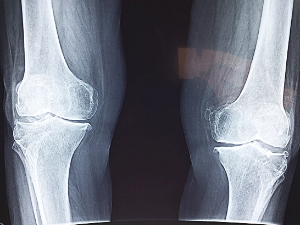

9. 십자인대 파열

무릎 관절은 앞뒤, 안팎의 안정성을 지키기 위해 4개의 인대로 지지되어 있습니다. 이들 중에서 두 쌍으로 구성된 4개의 인대는 십자가 형태를 띠고 있어, 이를 십자인대라고 부릅니다. 십자인대가 어떠한 원인으로 파열되면 무릎통증이 발생할 수 있습니다. 특히, 평소보다 무릎 통증이 심하고 부어오름이 느껴진다면 이는 십자인대 파열 가능성을 시사하는 신호일 수 있습니다.